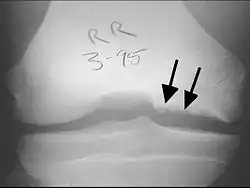

Tunnel or notch view X-ray of the right knee from a patient with osteochondritis dissecans—cystic changes and irregular border are indicated by arrows on the medial side compared to the lateral side

X-rays show lucency of the ossification on the anterior aspect of the knee in juvenile patients. In older people, the lesion typically appears as an area of osteosclerotic bone with a radiolucent line between the osteochondral defect and the epiphysis. The visibility of the lesion depends on its location and on the amount of knee flexion used. Harding described the lateral X-ray as a method to identify the site of an OCD lesion.[36]